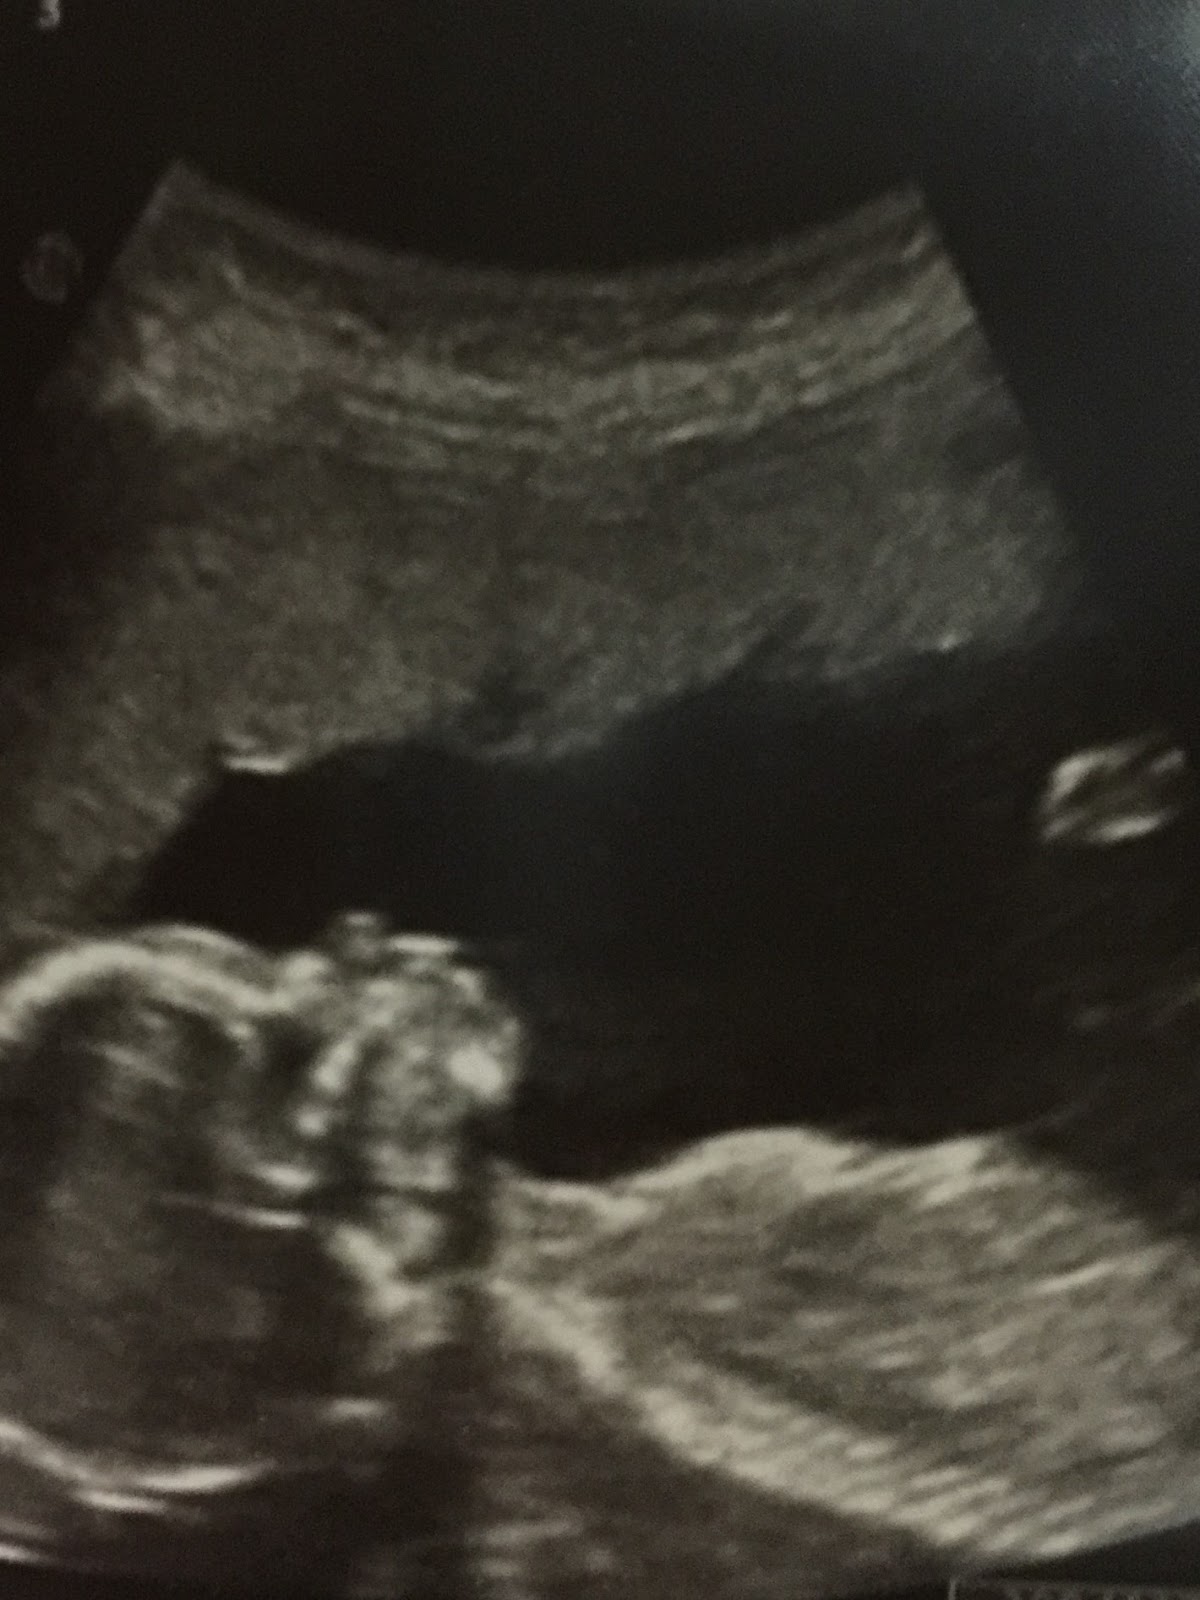

She added the text message, "My boy."

Those two words meant the world to me. This was a mother I met at the abortion center who spoke no English, but through the miraculous appearance of an interpreter who spoke her language, we were able to convince her to choose life for her unborn child rather than abortion. Over the next two months, I often received texts in broken English, saying, "Thanks you."